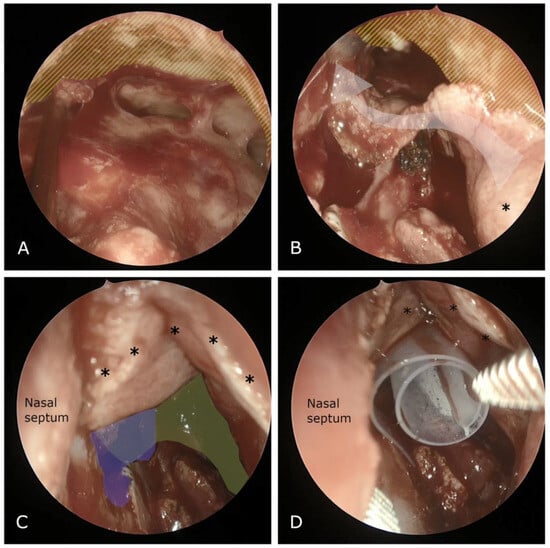

Another notable finding we observed was the high rate of neo-ostium closure in benign SNT. The vast majority of benign SNT cases in our cohort were osteomas—fourteen osteomas located in the frontal sinus, necessitating extensive drilling during surgery. It is well established, as noted by Rajapaksa et al. [19], that excessive drilling can contribute to restenosis (Figure 2 and Figure 3). Consequently, we hypothesize that this excessive drilling may account for the observed stenosis in this particular subgroup. The use of concurrent flaps and drug-eluding devices may offer a way to reduce neo-ostium stenosis in the future in such patients, and we are currently investigating this.

Figure 2. Intraoperative navigation image captured during a Draf III procedure aimed at frontal osteoma removal. Observe the extensive drilling necessary to access the lateral aspect of the lesion.

Figure 3. (A) CT scan of the same case, taken 3 weeks postoperatively. Observe the presence of the silastic sheet (indicated by the white arrow); (B) subsequent follow-up image, captured 6 weeks postoperatively. The neo-ostium is prominently open, and the flap is thoroughly integrated (asterisks).